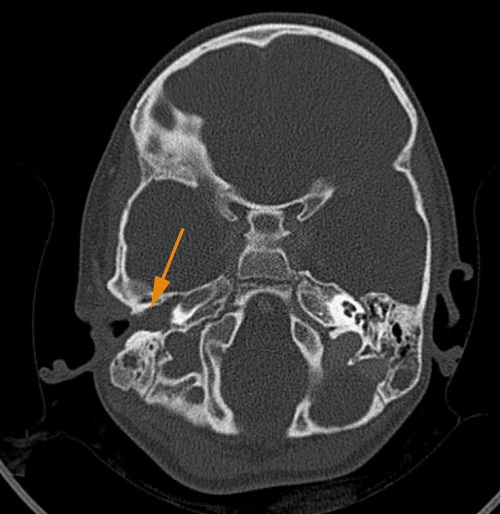

Al día siguiente tienen consulta telefónica en Atención Primaria y los padres refieren que la niña está muy mareada, tiene dolor que no consiguen controlar con analgesia habitual y, aunque está tomando amoxicilina, a veces vomita la dosis y tienen dudas sobre si le está haciendo efecto. En ese momento se indica a los padres que la traigan de nuevo presencialmente. En la exploración ya destaca el mal estado general de la paciente, la traen en carro porque tiene dificultad para ponerse en pie y caminar, el oído derecho persiste supurado y tiene dolor a palpación en región mastoidea derecha, con leve hiperemia de la zona retroauricular. Comentan además que han observado que tiene fotofobia. Ante la sospecha de mastoiditis complicada, se deriva de nuevo a urgencias, donde finalmente se realiza tomografía axial computarizada (TAC) craneal, objetivándose hallazgos compatibles con otomastoiditis derecha complicada con trombosis venosa ipsilateral, con afectación del seno transverso, sigmoideo y yugular (Figuras 1 y 2). Se inicia tratamiento intravenoso (iv) con cefotaxima 300 mg/kg/día, metronidazol 30 mg/kg/día y vancomicina 60 mg/kg/día, corticoterapia iv y sueroterapia. Se realiza mastoidectomía con drenaje en tubo en T transtimpánico y posteriormente tratamiento tópico con gentamicina y dexametasona. Además, se inicia tratamiento con enoxaparina a 1 mg/kg cada 12 horas. El cultivo del exudado ótico es positivo para Streptococcus pyogenes grupo A. La paciente evoluciona favorablemente. Durante el ingreso se descarta afectación cardiológica y a nivel neurológico presenta buena evolución con exploración neurológica al alta normal.

Figura 2. Imagen en TAC en la que se aprecia ausencia de ventilación en la mastoides derecha